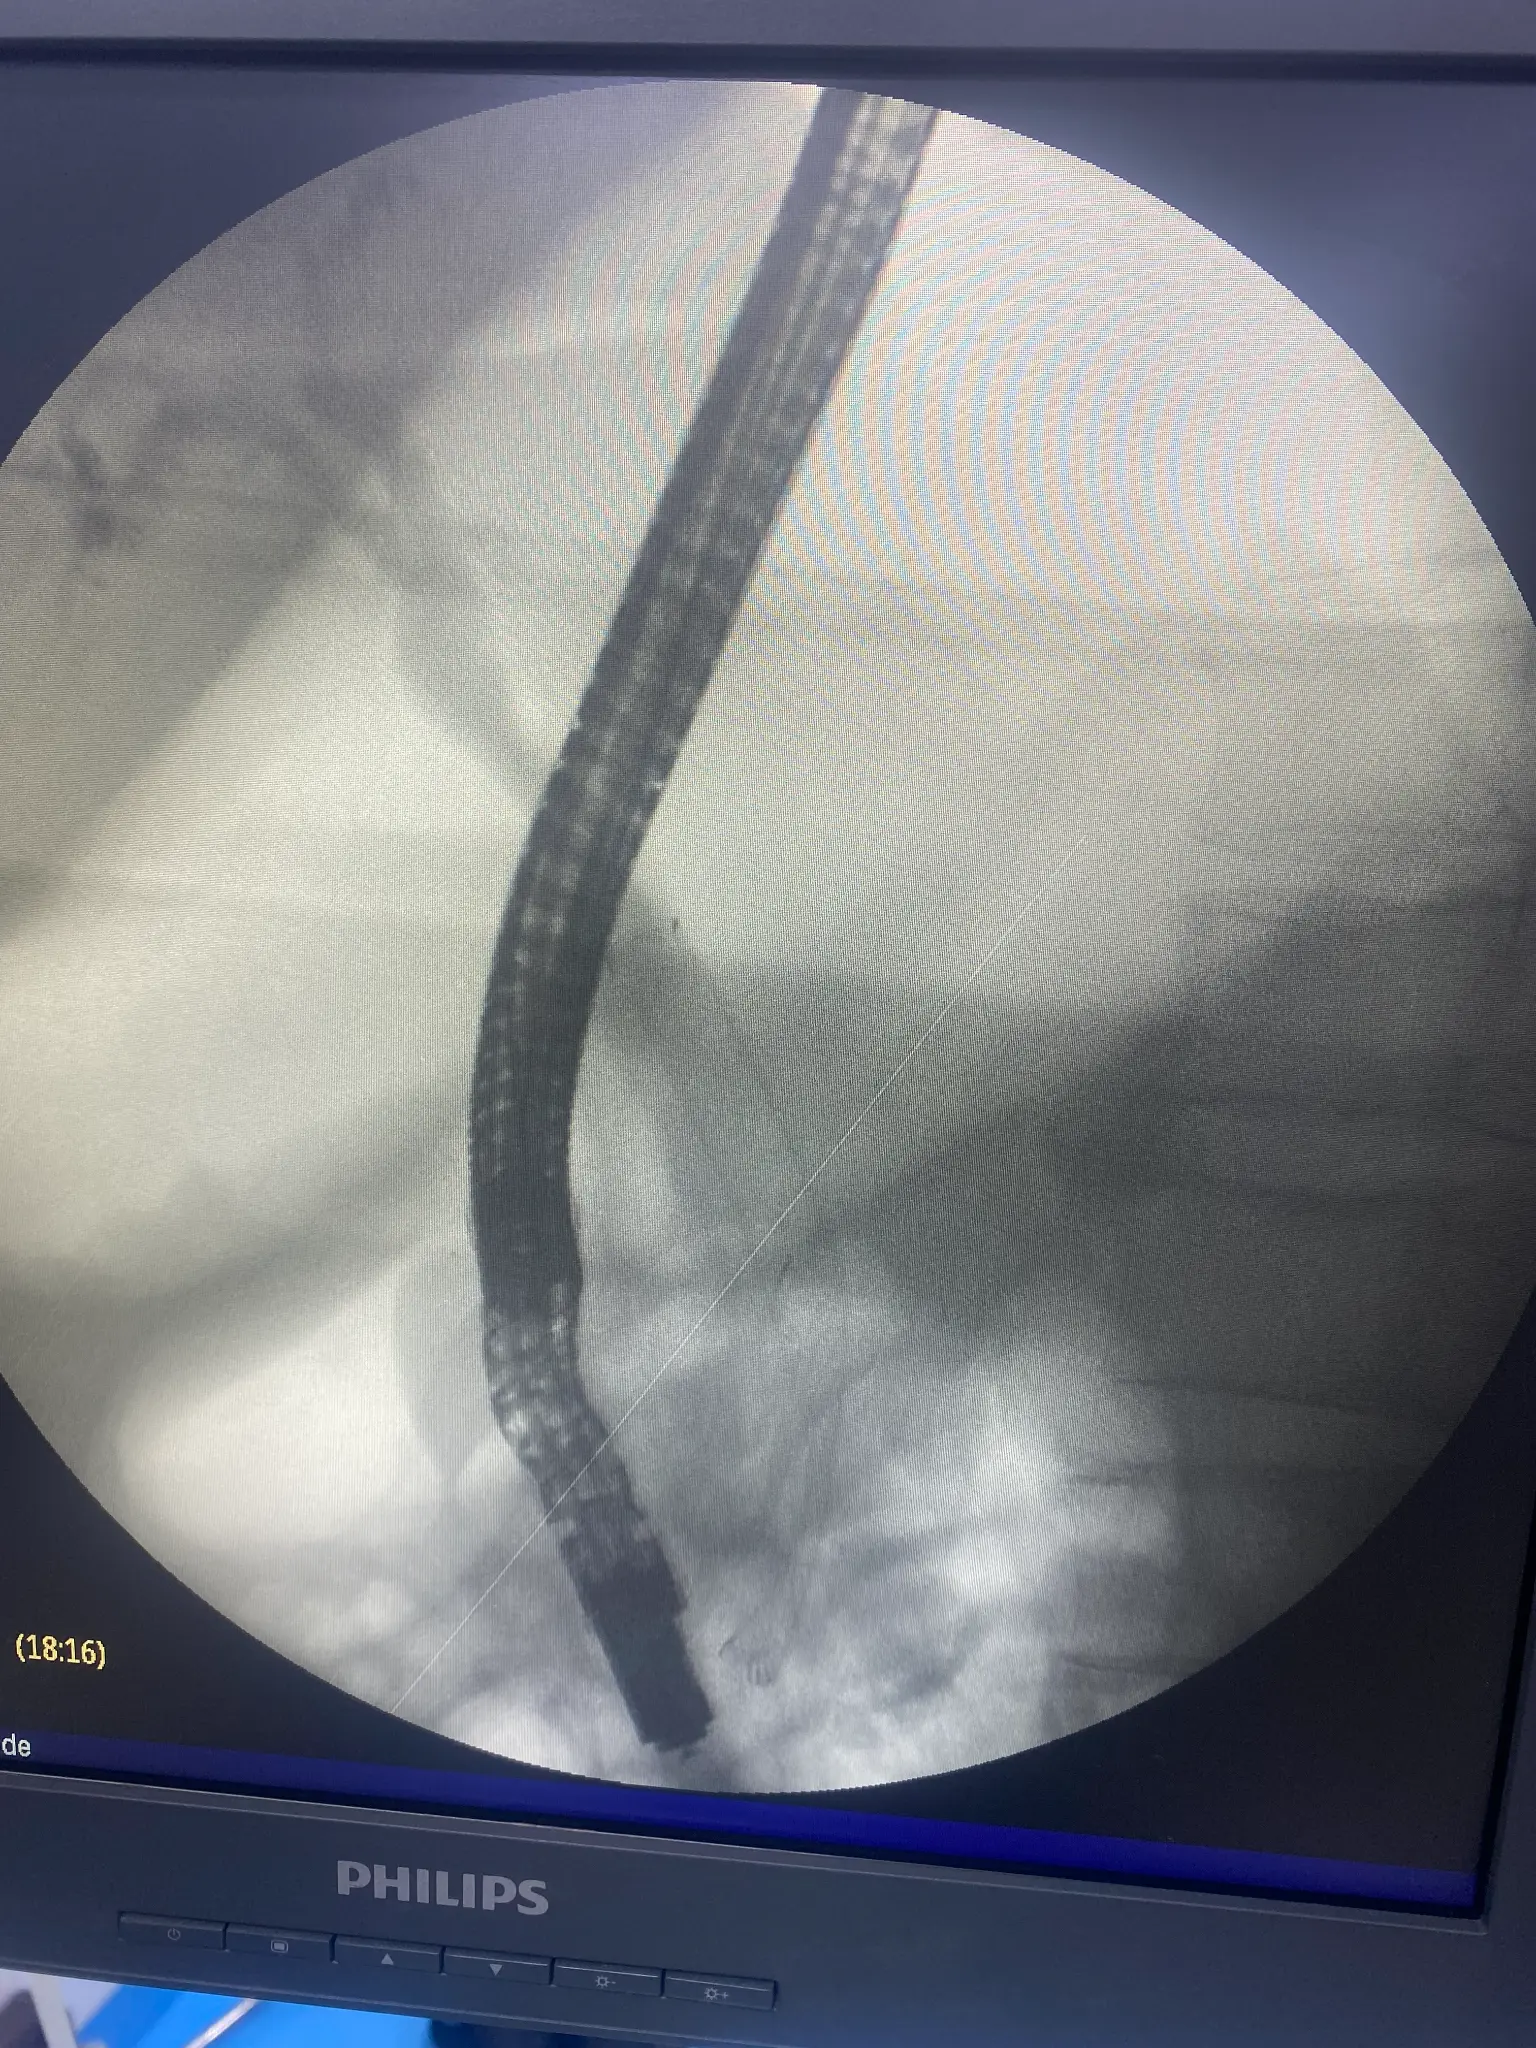

ERCP Intervention Photos

Placement of plastic or metal stents to keep bile ducts open when narrowed by tumors, strictures, or inflammation. Stents restore bile flow and relieve jaundice.